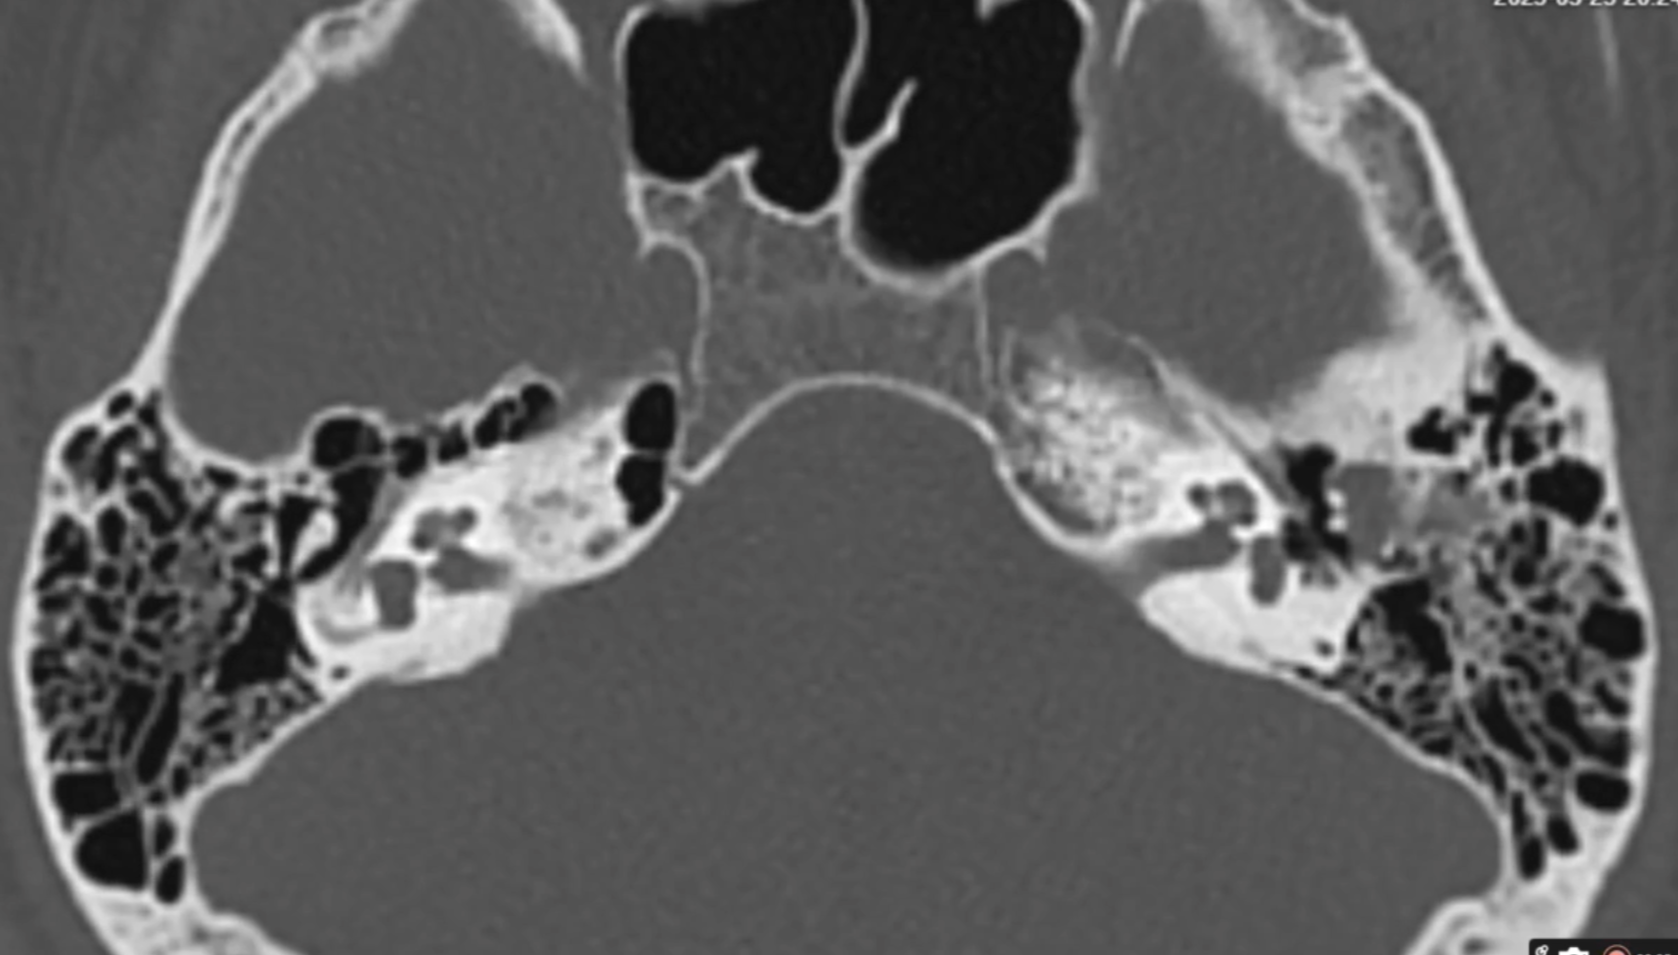

MRI Scan Analysis CT Scan Analysis Temporal Scan Analysis Orbits Scan Analysis MRI Scan Analysis CT Scan Analysis Temporal Scan Analysis Orbits Scan Analysis

MRI Temporal Bones: ₹1000

CT Temporal Bones: ₹1000

MRI Paranasal Sinuses: ₹1000

CT PNS: ₹1000